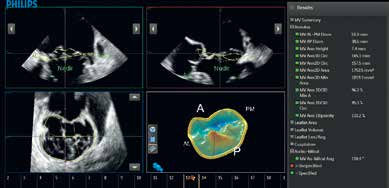

二尖瓣导航 (MVNA.I.)

二尖瓣导航(MVNA.I.)是旨在获得二尖瓣实时三维容积并通过八个引导下的步骤将其转化为易于解读的模型,提供二尖瓣测量和计算的全面列表。跟以往的工具相比,二尖瓣导航建模和测量减少了89%的点击次数。

二尖瓣导航 (MVNA.I.)在处理过程的每一部分中减少步骤:

• 瓣环数据的获取减少了74%的点击,同时在无用户交互的情况下提供了自动瓣叶描记。

• 二尖瓣导航(MVNA.I.)使用简单的指令和清晰的图形来引导整个处理过程,使之比以前的二尖瓣量化工具更容易使用。

• 二尖瓣导航(MVNA.I.)的结果完成时可在屏幕显示,加速访问所需数据的过程。

二尖瓣导航(MVNA.I.)获取二尖瓣的实时三维容积,并在短短的8个引导步骤下将之转化易于解读的模型。